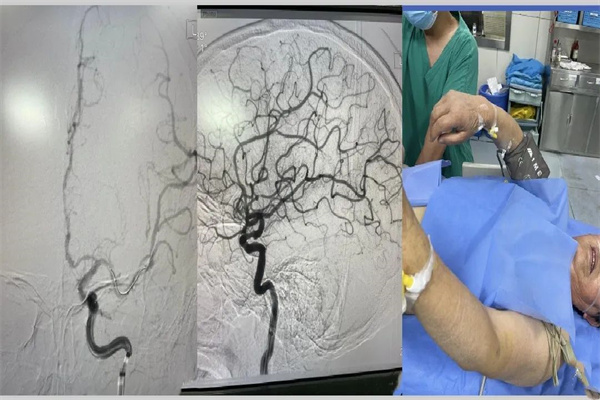

“趕快登記顱腦磁共振檢查,安排病人完善檢查!”我快速?zèng)_進(jìn)影像科登記室,拿著登記好的檢查單,立馬又送往了檢查室,安排檢查。整個(gè)過(guò)程在上級(jí)醫(yī)師的指導(dǎo)下快速而又清晰的進(jìn)行著。來(lái)不及我多想什么,很快結(jié)果出來(lái)了,左側(cè)額葉大面積梗死,左側(cè)大腦中動(dòng)脈上干閉塞,立刻安排急診介入血管再通治療。

8分鐘,從股動(dòng)脈穿刺成功到血管再通。61分鐘,從入院到股動(dòng)脈穿刺成功,我們成功的贏取了寶貴地時(shí)間,挽救了患者快速流逝的生命!

患者從昏迷到清醒,從右側(cè)肢體完全癱瘓到可自主抬起患肢,這就是我們的答卷,也是綠色通道真正的意義所在,卒中綠色通道,生命的通道!